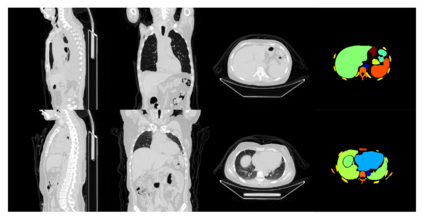

In recent years, deep learning methods such as convolutional neural network (CNN) and transformers have made significant progress in CT multi-organ segmentation. However, CT multi-organ segmentation methods based on masked image modeling (MIM) are very limited. There are already methods using MAE for CT multi-organ segmentation task, we believe that the existing methods do not identify the most difficult areas to reconstruct. To this end, we propose a MIM self-training framework with hard patches mining masked autoencoders for CT multi-organ segmentation tasks (selfMedHPM). The method performs ViT self-pretraining on the training set of the target data and introduces an auxiliary loss predictor, which first predicts the patch loss and determines the location of the next mask. SelfMedHPM implementation is better than various competitive methods in abdominal CT multi-organ segmentation and body CT multi-organ segmentation. We have validated the performance of our method on the Multi Atlas Labeling Beyond The Cranial Vault (BTCV) dataset for abdomen mult-organ segmentation and the SinoMed Whole Body (SMWB) dataset for body multi-organ segmentation tasks.